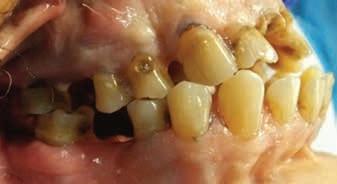

A 44-year-old female patient presented to the general dentistry clinic at the University of California, Los Angeles with a chief complaint of wanting to replace her missing posterior teeth. Her last dental visit was more than 10 years ago. Past medical/surgical history was significant for right sided brain arteriovenous malformation (AVM), seizure disorder secondary to the AVM, stroke, endometrial cancer, and an SRT regimen of 30 Gy in 5 fractions over the span of 6 years. On extraoral examination, the patient reported non-painful clicking on the right temporomandibular joint with mild tenderness of the masseter muscles bilaterally. Intraoral

Radiographic examination:

examination revealed multiple moderately deep carious lesions, abrasion and attrition on the posterior molars and a non-restorable upper right first molar.

Her full mouth intraoral radiographs revealed generalized pulpal calcifications of various dimensions in the pulp chambers and root canals. In at least one tooth, multiple discrete pulpal calcifications were observed. All teeth with existing pulpal calcifications were asymptomatic, and did not show any radiographic signs of periapical bone loss or periodontal ligament (PDL) widening.

Figure 1. Full mouth radiographic survey reveals multiple pulpal calcifications of various dimensions affecting the pulp chamber and radicular pulp of patient’s remaining dentition.

Figure 2. Full mouth radiographic survey reveals multiple pulpal calcifications of various dimensions affecting the pulp chamber and radicular pulp of patient’s remaining dentition. Multiple discrete pulpal calcifications can be noted on upper left first molar pulp chamber.

Figure 3. Mounted casts showing lack of posterior support in the upper right side, anterior attrition and crowding.